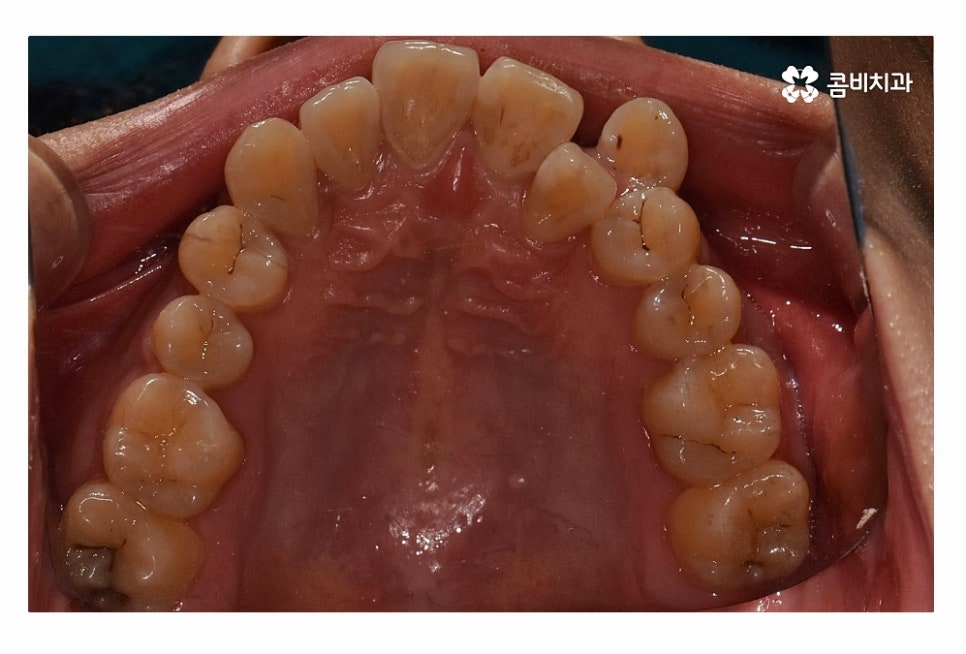

오늘 보시는 환자분의 사례처럼 덧니가 치아끼리 겹쳐 있는 경우에

치아의 이동 공간 확보를 위해서 덧니 발치 필요한 사례였으며

교합과 치아교정 후 얼굴 변화를 고려할 때도 치아교정 과정에서

발치가 필요한 사례였다고 볼 수 있어요.